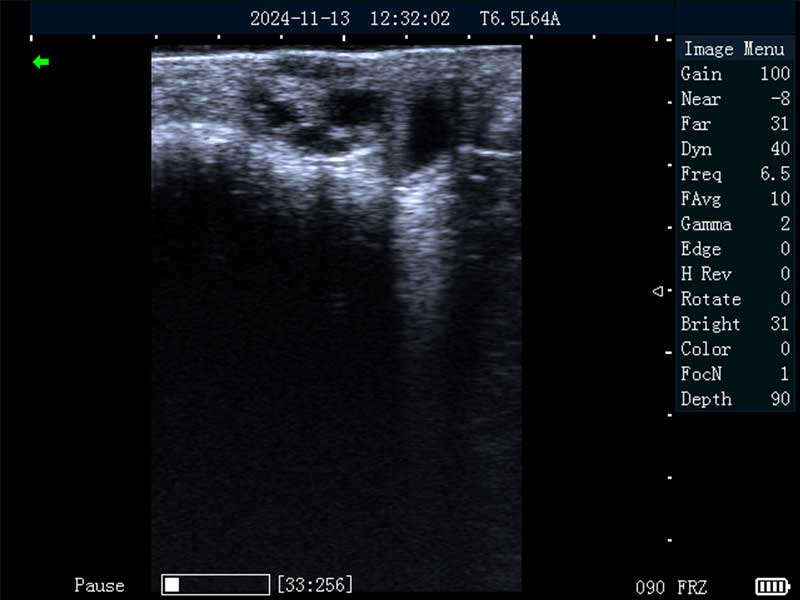

牛黄体

牛卵巢

牛妊娠40日龄

牛妊娠65日龄

马妊娠30日龄

马妊娠100日龄

马妊娠26日龄